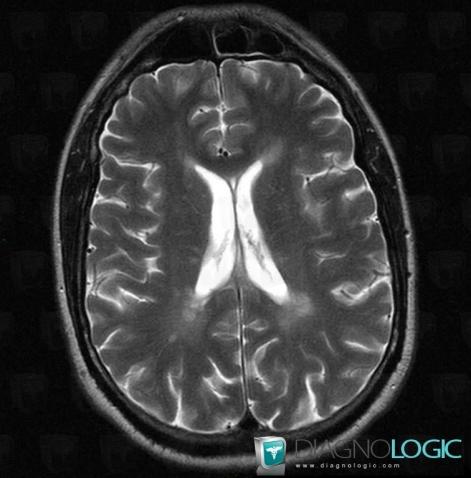

Multiple sclerosis, Cerebral hemispheres, MRI

Here is the specific information in the key image above:

- Diagnosis Multiple sclerosis, Location(s) Cerebral hemispheres, with gamuts White matter disease, Multifocal intracranial lesions, Intracerebral T2W or FLAIR hyperintense lesion